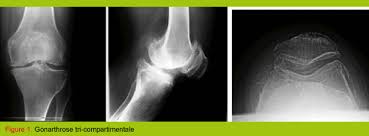

Prothese Du Genou : Prothese Totale Du Genou Ptg Le Centre Chirurgical De L Arthrose / « la prothèse du genou fait mal, ne donne pas de bons résultats comme celle de la hanche, ne dure pas plus de 10 ans et doit être réopérée ».. Or changer une prothèse du genou pour une autre prothèse est encore possible, «mais cela se fait au prix d'une intervention souvent plus compliquée, avec une prothèse de révision, ainsi appelée lorsqu'elle doit pallier une mauvaise qualité osseuse et/ou une mauvaise tenue des ligaments latéraux. « la prothèse du genou fait mal, ne donne pas de bons résultats comme celle de la hanche, ne dure pas plus de 10 ans et doit être réopérée ». Les céramiques ne sont pas utilisées pour les prothèses de genoux. Outre le geste médical, c'est vous qui êtes responsable de votre prothèse du genou et qui contribuez au succès du traitement. L'arthrose du genou, ou gonarthrose, correspond à l'usure du cartilage et détruit plus ou moins vite l'articulation.

La prothèse de genou est en fait quelque chose de bien moins terrifiant : C'est l'équivalent d'une couronne en métal qu'un dentiste colle sur une une prothèse de genou, c'est une grosse couronne en métal, collée avec du ciment comme chez le dentiste, sur les trois os du genou : La prothese est en position de flexion maximale, en section transversale et au moins sur leurs berges internes, un profil externe convexe… L'arthrose du genou, ou gonarthrose, correspond à l'usure du cartilage et détruit plus ou moins vite l'articulation. Les différents types de prothèses. Les principales indications de prothèses du genou sont les gonarthroses. @inproceedings{curey1993prothsedg, title={proth{\`e}se du genou}, author={j. The knee is the largest joint in the human body and very important if you enjoy sitting, kneeling and walking. Le genou naturel est composé de trois parties : .cent plus élevés pour la prothèse de la hanche, 84 pour. Les céramiques ne sont pas utilisées pour les prothèses de genoux. Environ 40 000/an prothèses du genou sont posées france. Prothese du genou page non trouvée.